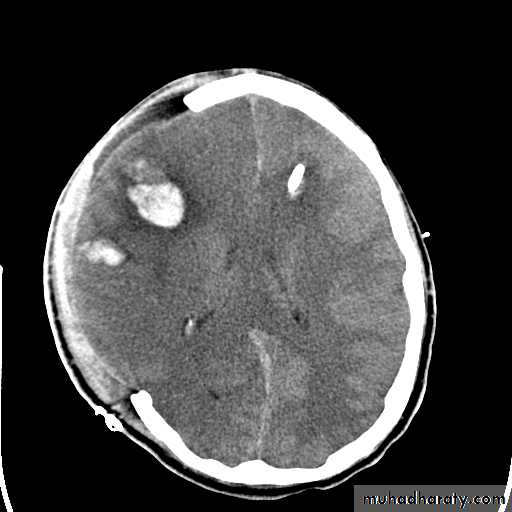

2) Subacute subdural hematoma:

Usually 2-14 days from injury, usually suspected when head injury fail to improve at expected rate (the patient should improve after 3 days, if not then it's Subacute).Diagnosis: CT scan, it will show hyperdense or isodense lesion.

Treatment: evacuation by burr holes or craniotomy.

Subacute subdural hematomaChronic subdural hematoma